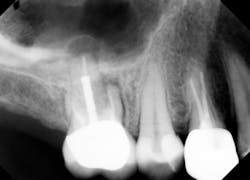

Therefore, if a patient has 5 mm of available bone height from the sinus floor, a maximum of 5 mm is prudent to expect from an indirect lift; therefore, an 8 mm to 10 mm implant is the ideal choice. The tapered iHex or MorsTorq implant provides safety when dealing with sinus areas, for three reasons. First, the taper helps prevent overinsertion toward the sinus cavity. Second, the abutment and transfer attached to the implant allows for more control. Finally, the rounded apex helps reflect the sinus floor without creating damage (figures 1-6).